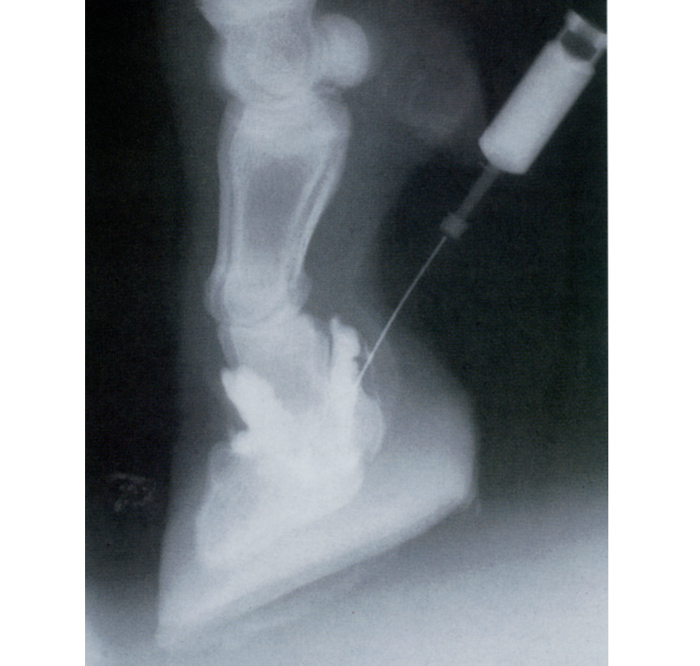

In animals suffering from a very painful digital condition, regional anaesthesia by interdigital nerve block or intravenous regional anaesthesia may have to be resorted to in order to carry out an adequate examination and application of local treatment. Both techniques are quick and simple. However, it should be realized that an interdigital nerve block anaesthetizes only the axial aspects of the digits; hence, it is not suitable for treating lesions that are located abaxially. It is performed by injecting 20 ml of a suitable local anaesthetic solution between the digits 20 to 30 mm distal to the fetlock while the animal is in a standing position and lightly sedated, at the same time restraining it by lifting its tail and pushing the latter forward.

When using intravenous regional anaesthesia any accessible and prominent superficial vein situated distal to a previously applied tourniquet may be chosen. The most common site for the hindlimb is the lateral branch of the saphenous vein, and for the forelimb the medial branch of the cephalic vein. Alternatively, it may be easier to use the dorsal common digital vein III, or to tap into any venous plexus on the dorsal or plantar/palmar aspect of the limb, exactly in the midline and 2 to 3 cm below the fetlock joint (i.e. at the level of the proximal interdigital joint).95

A strong rubber tourniquet is placed around the limb just below the tarsal/carpal region and the vein palpated immediately proximal to the fetlock joint. The area over the vein is disinfected and 10 to 20 ml of a 2 per cent lignocaine solution (without adrenaline) is injected intravenously using a 20 gauge needle. Analgesia starts to develop after two to three minutes and is complete within 10 minutes. The interdigital region is the last area to become fully numb and increased amounts of anaesthetic solution (up to 30 ml) may be required to achieve adequate analgesia.95 After releasing the tourniquet, sensation and motor function return to normal in about five minutes.